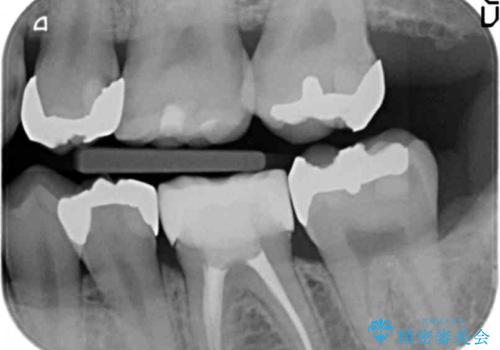

奥歯の詰め物のやりかえ セラミックインレー、ゴールドインレー

- 上の奥歯の詰め物が合っていないため、やりかえを行いました。

- 20万円 内訳 左上56:emaxインレー7万円x2 、左上7:PGAインレー6万円 (税別)費用は治療当時の料金となります

上の一番奥の歯は、一番目立たない場所なので(他人から見えない)、ゴールドインレーでも目立ちません。

セラミックインレーでは割れやすい大きさの虫歯または、歯が薄くなって被せなければいけないような場合でも、金属(ゴールド)は耐久性があり、クラウン(被せ物)にしなくて済みます。